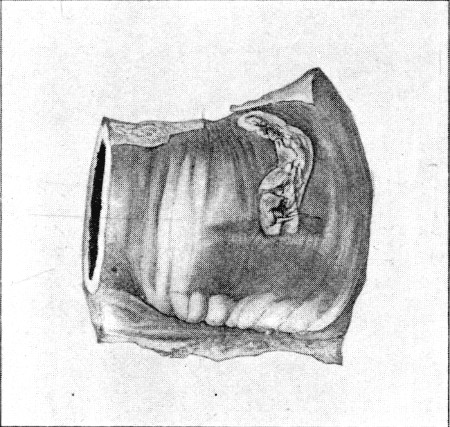

25b. Prolapsed Omentum77

89. Impaction of Omentum in Exit Wound of Abdominal Wall421